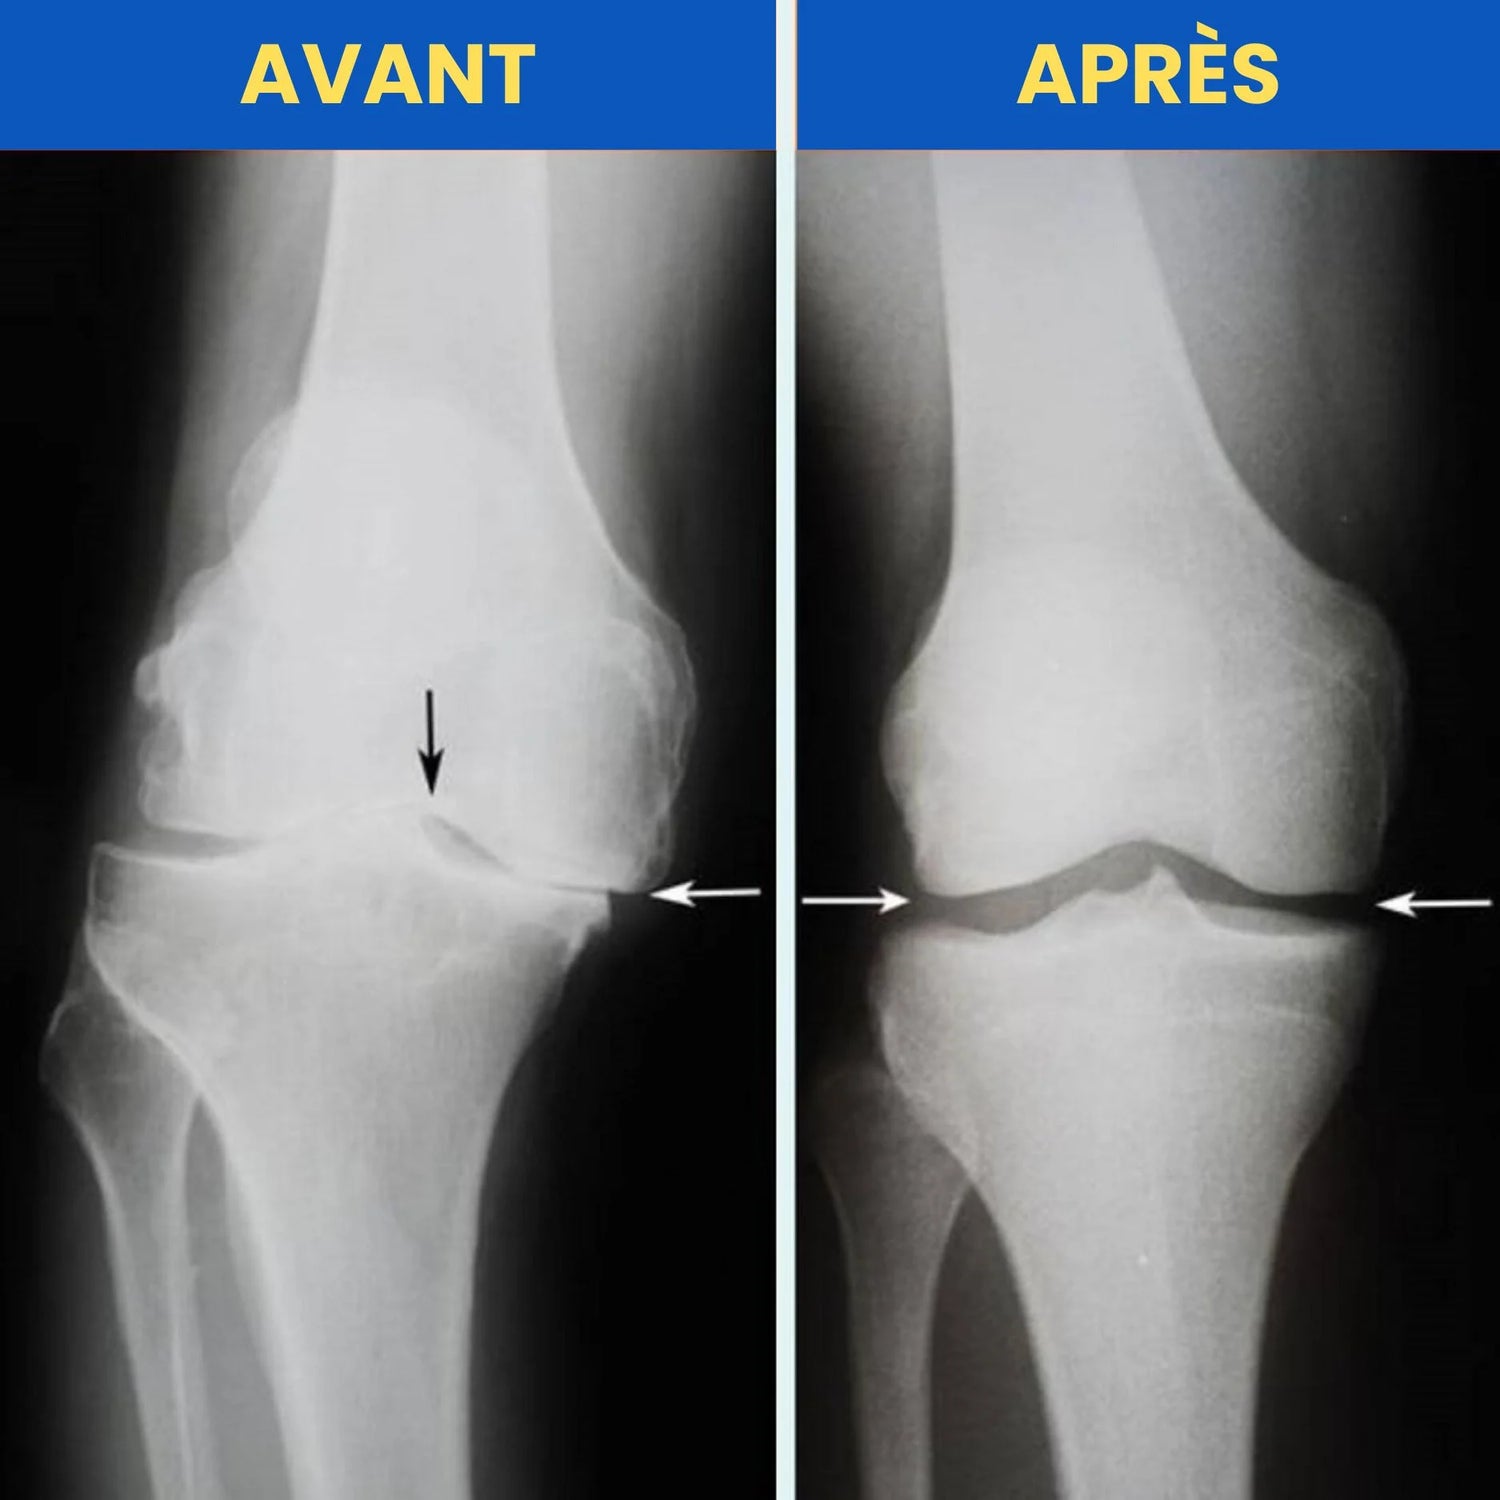

Lorsque le genou est mal aligné, chaque mouvement peut aggraver les douleurs.

Grâce à la Technologie d’Alignement Biomécanique, FlexiGenoux™ réaligne naturellement la rotule, réduit la pression sur le cartilage et soulage la douleur à la source.

Résultat : plus de stabilité, moins de tension, une marche fluide et un genou qui retrouve sa fonction naturelle.